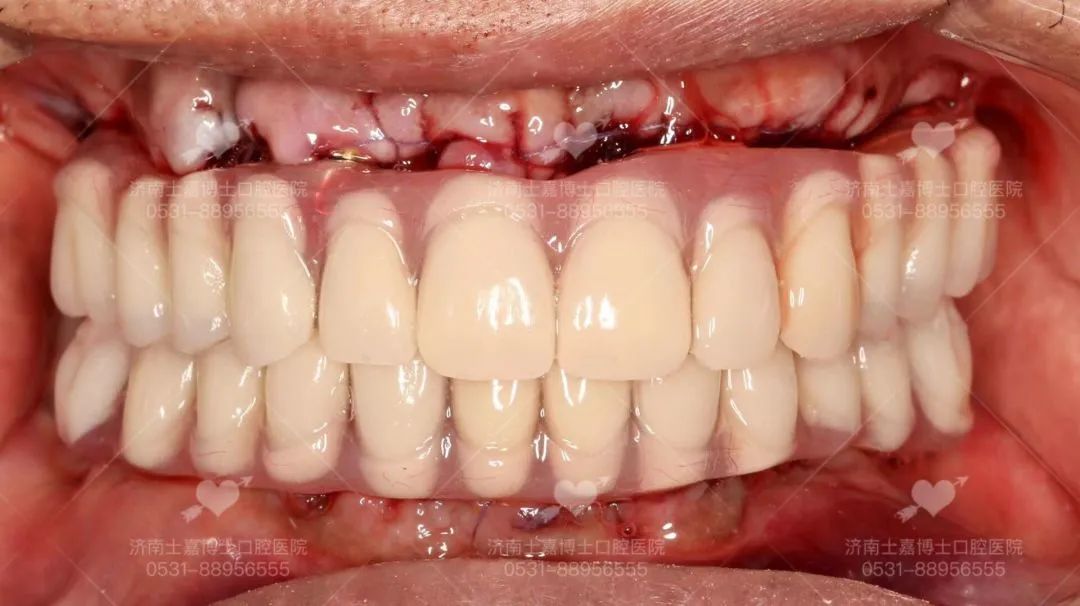

医生技术好 · 种牙不受罪 · 牙齿用到老 种植牙的成功与长久使用,与医生的医疗技术和水平及医院的设备有着直接的关系。那么由谁种,是种植牙成功的关键! 下面将从几个方面来看,如何选择一个好的种植医生。 一、看学历/资质 学历背景很重要,尽量选择口腔医学院校毕业的医学生,这些在专业口腔医学院校接受的培训和掌握的技术更规范和先进,水平较高的种植医生一般都是硕士、博士级别。 二、看进修背景 种植科医生会不断进修,一般选择口腔专科医院或是大型综合三甲医院口腔科或是国外的牙科学院进行进修学习 三、看种植技术,尤其是复杂种植完成质量 医生技术好,种植后就极少出现种植体与骨之间愈合不好而导致的牙松动、脱落等,越能把握种植牙长期效果,尤其是针对复杂牙种植后的完成质量,更是“一牙见分晓” 种植过程中,技术好的医生对种植体植入到牙槽骨的把握力度更好,对于基台穿龈的准确度就越高,为保证种植牙长久的使用打下良好基础 尤其是中老年人普遍面临着半口/全口缺牙、长期缺牙、牙槽骨萎缩吸收等难题,传统种植技术对老人身体损伤较大,导致无法实现种牙。而娴熟掌握先进技术的种植医生,能够做到少植骨或不植骨,更能保证种植后的效果和质量 四、看种植案例数量 种植牙是一项精细的医学手工技术,一般来说,临床经验越丰富,医生技术就会越好,种了100颗牙与种了10000颗牙的医生,在技术经验是有很大差别的,针对牙齿种植,所种植的数量越多,就能更好的帮患者患者减少种植过程中的手术痛苦、保证种植牙的长久使用 所以,选择医生一般都会选择种植经验丰富,这在很大程度上决定了种植牙后期的使用效果以及使用寿命 士嘉博士口腔医院舒适化种植团队 从种植体设计、生产,到医生把种植体植入牙槽骨,再到完成种植后患者的个人生活习惯,每一个环节、每一个细节都会影响种植体表面骨改建的动态平衡,继而影响种植成功还是失败。 因此,选择一个有经验有技术的种植医生尤为重要。 张士杰,山东大学口腔医学院博士研究生导师、教授、博士后,山东大学齐鲁医院口腔正畸科主任、主任医师。中华医学会口腔正畸专业委员会委员,中华医学会整形美容牙颌颜面美容分会常委,世界正畸联盟WFO会员。曾赴日本东京医科齿科大学、美国康州大学牙医学院、美国哈佛大学种植研修中心访问交流。发表学术论文四十余篇,其中被SCI收录十五篇,获山东省科技进步三等奖一项。承担国家自然科学基金、山东省自然科学基金、山东省科技攻关、山东大学自主创新、山东省重大专项等多项科研项目。口腔临床技能全面,以先进技术为基础、结合国外口腔诊疗服务理念,通过口腔正畸、种植修复、牙周治疗、牙齿美容等全面为患者提供适合的治疗方案,注重人文关怀。 擅长:成人及青少年各类牙齿畸形的矫正治疗,隐形矫正(山东省首批美国隐适美隐形矫正认证专家),在诊疗牙齿前突、开唇露齿、地包天、唇腭裂等正畸正颌联合手术治疗方面尤其突出,尤其擅长复杂牙列缺失的种植修复和咬合重建治疗。 高万郝,主治医师,山东大学口腔医学硕士,北京大学口腔医学院进修 擅长:各类牙齿种植、智齿拔除等口腔手术,熟练掌握多套国际先进的种植系统有多年口腔种植临床经验,尤其擅长复杂病例的咬合重建 病例分享一:77岁老人全口种植 父亲节当天,77岁的老人来士嘉博士口腔全口种植,老人得过脑梗、有心衰,本不想做牙齿上的治疗,在儿子坚持下做了种植,当天做到即刻拔牙即刻修复即刻全口种植,拔牙后吃上肉包子,由衷的感叹:香! 病例分享二:80岁奶奶上半口种植初体验 奶奶说“效果很好,牙齿很漂亮,一点都不痛!” 五、看选择的种植机构 口腔种植学,不仅是独立的学科,且涉及口腔颌面外科学、修复学、牙周病学、材料学、生物力学、影像学等口腔各学科领域。 先进的种植仪器 士嘉博士口腔医院坚持设备与国际同步,倡导舒适化的诊疗理念 我们引进了德国卡瓦3D数字化影像设备、德国3D瓷睿刻数字化牙椅旁修复系统、德国3D打印数字化种植导板系统、瑞士美国德国韩国等世界品牌种植系统等 能够提供当天就诊、当天戴牙,大大缩短了患者的等待时间。个性化服务更好,义齿生产质量更精密,还能快速解决临床戴牙所遇到的问题,更舒适、效率更高,客户满意度大大提高